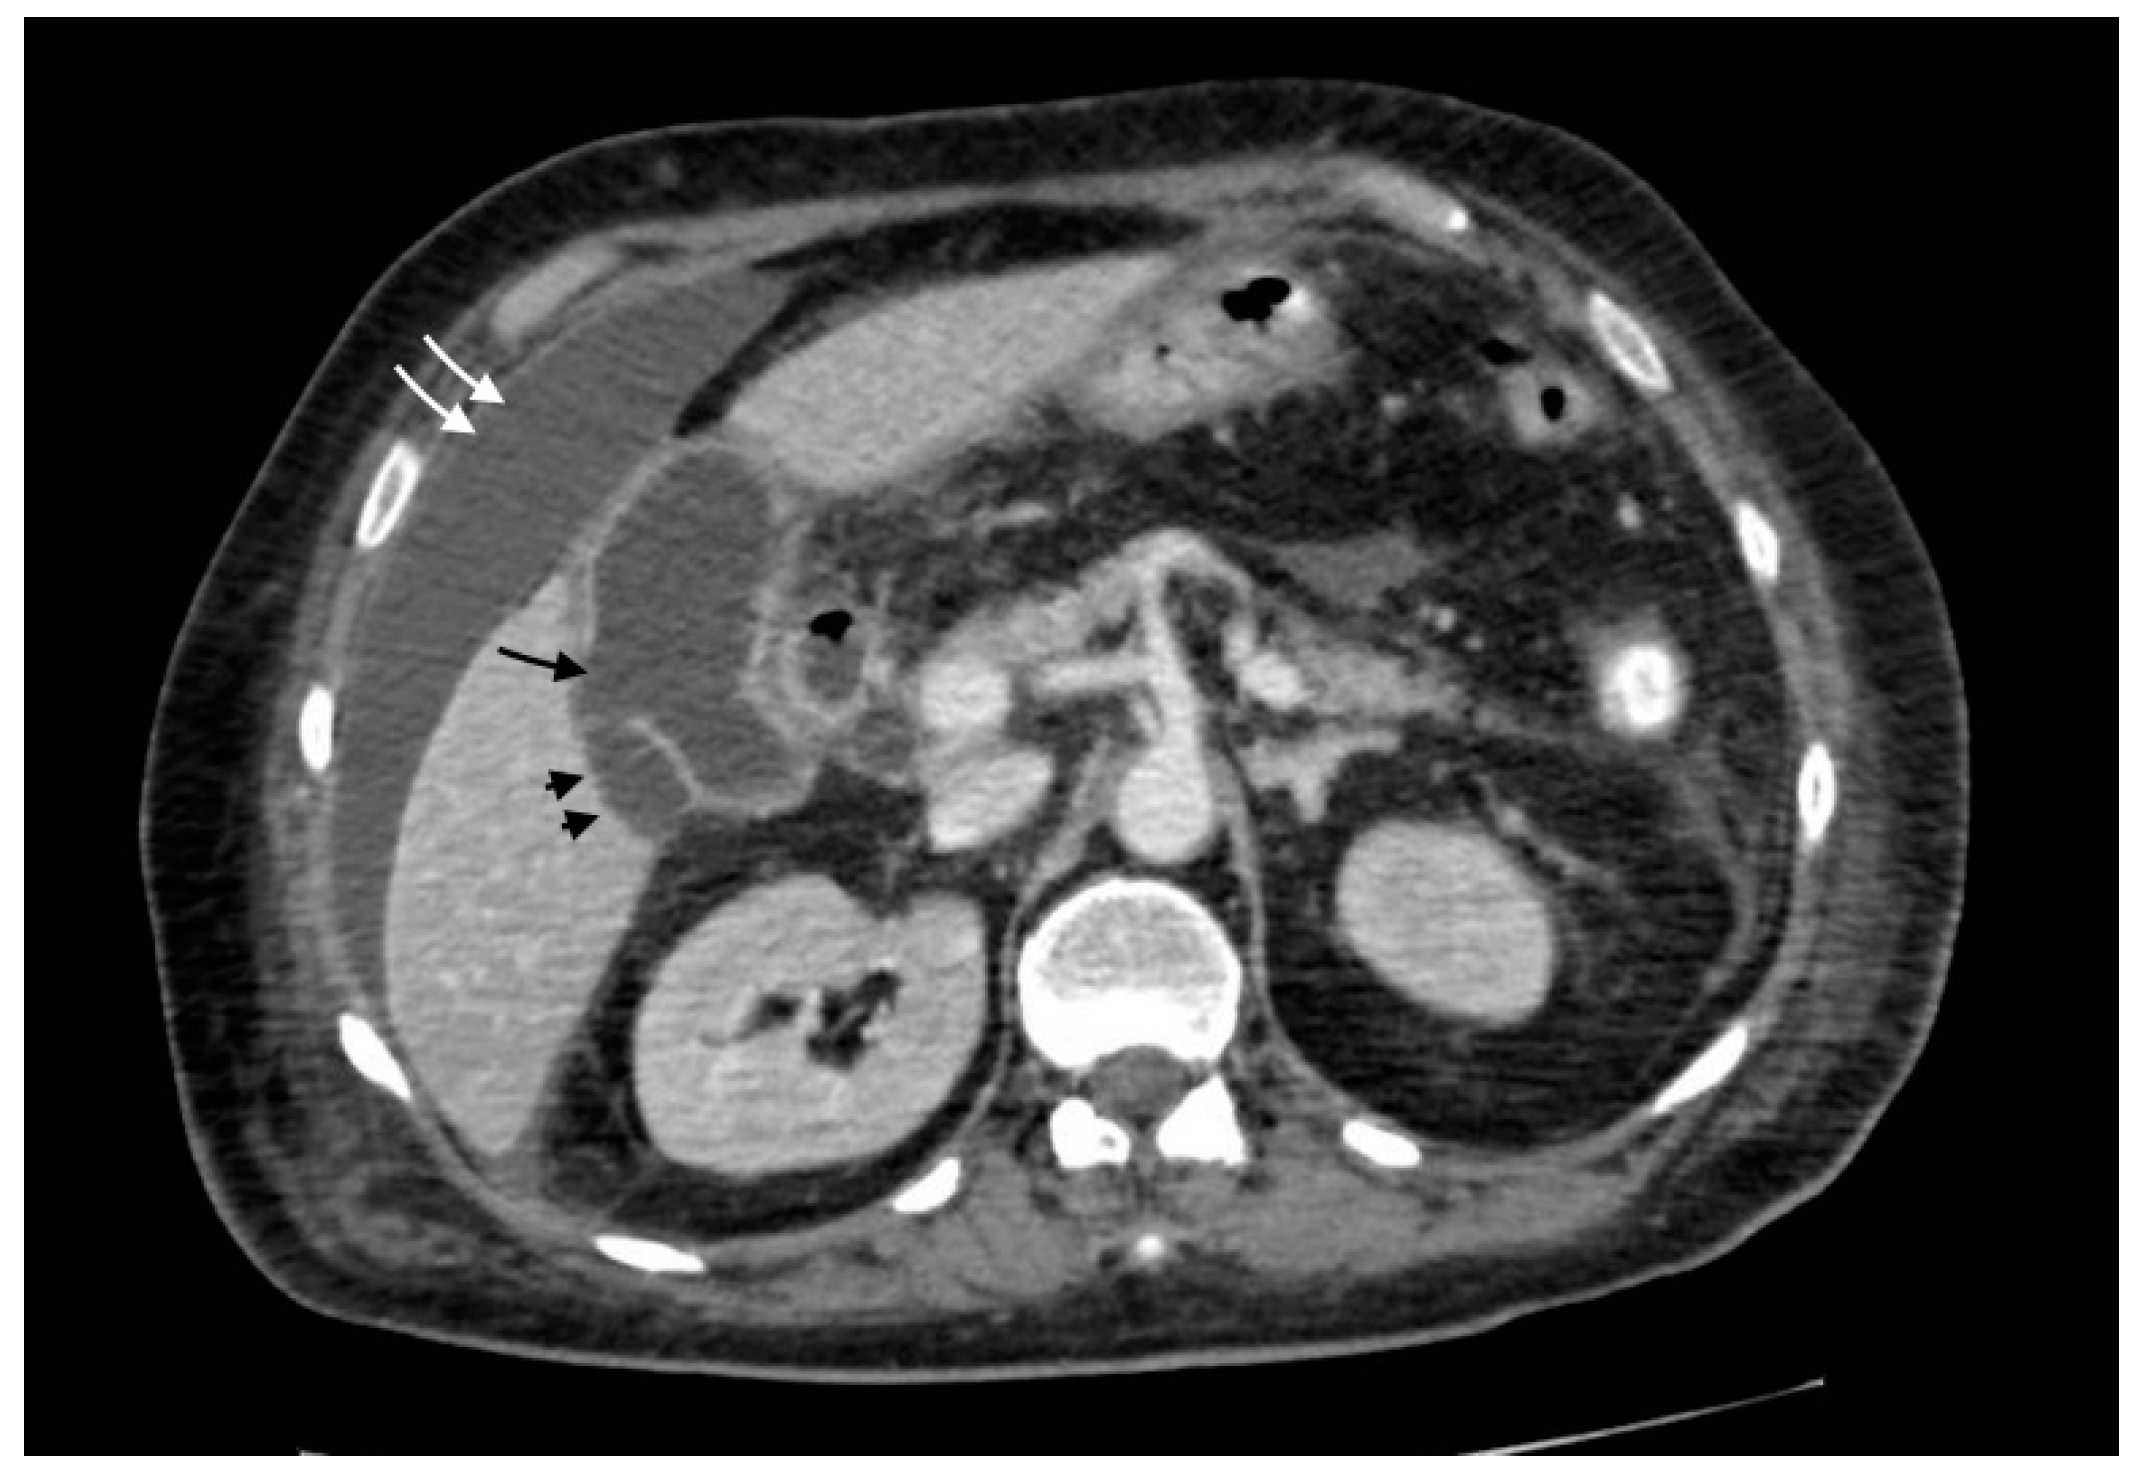

Figure 4.

Gallbladder perforation: transmural defect of the gallbladder wall (black arrow) with pericholecystic effusion (head arrows) and perihepatic peritoneal collection, suggestive of biliary peritonitis (white arrows).